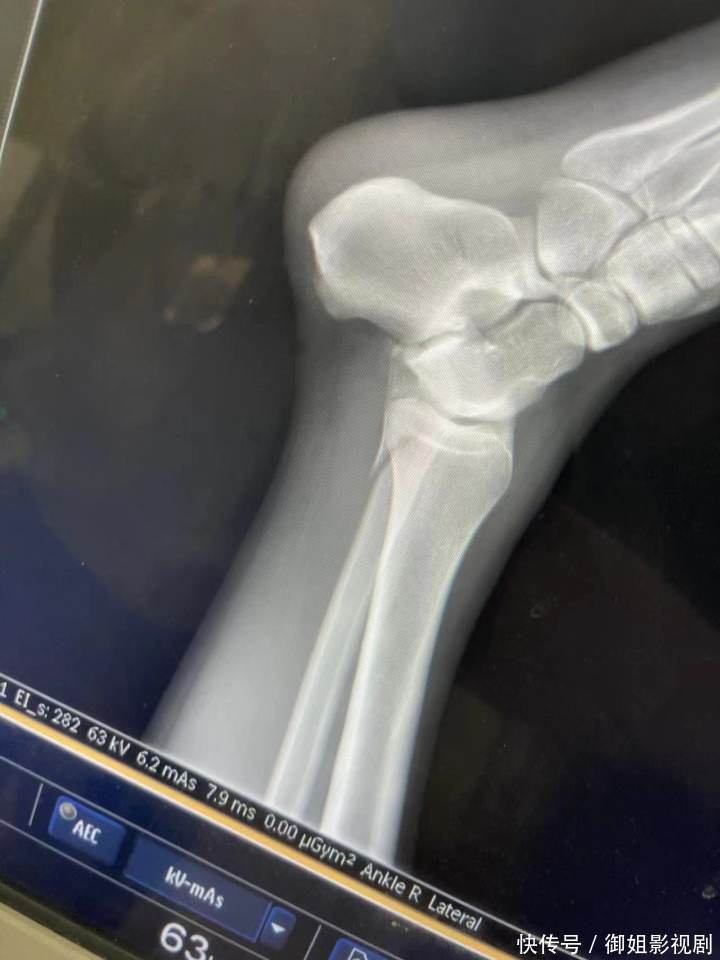

贝博龙虎斗橙柿互动把稳到,有受伤的女孩还在视频平台直播,回报我方受伤的经过。女孩称,我方冲关时摔下来,腿齐骨折了。

“我就把躺的位置让给她,她的腿骨折了,我是踝骨受伤。现场的责任主说念主员让咱们到二级以上的公立病院诊治,然后报销。

“大夫会诊,我腿上的胫骨腓骨同期断裂。从景观送到病院救护车的钱,齐是我和小董一东说念主一半我方付费的,连诊治用度齐是咱们我方垫付的。”